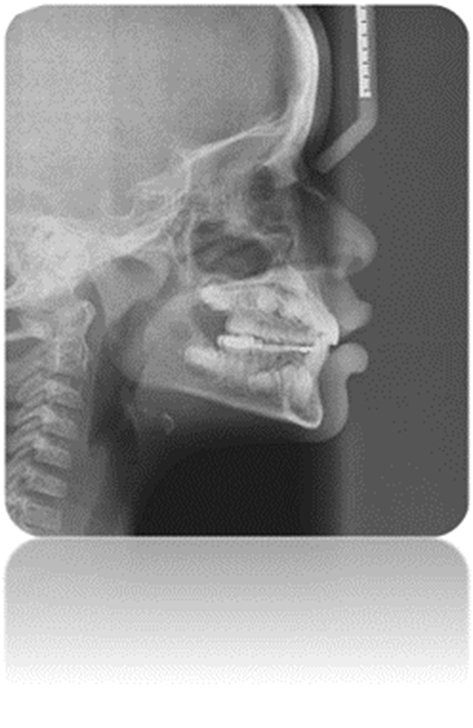

Figura 20. Radiografía de perfil post tratamiento.

Autor: María Gabriela Flores Bracho. Fuente: Historia Clínica R.O. 4 años. 2017. Paciente con mordida cruzada anterior, clase I molar y caninos

Figura 21. Fotografías de frente y perfil.

Autor: María Gabriela Flores Bracho. Fuente: Historia Clínica R.O. 4 años. 2017. Paciente con mordida cruzada anterior, clase I molar y caninos, desvio de. Línea media.